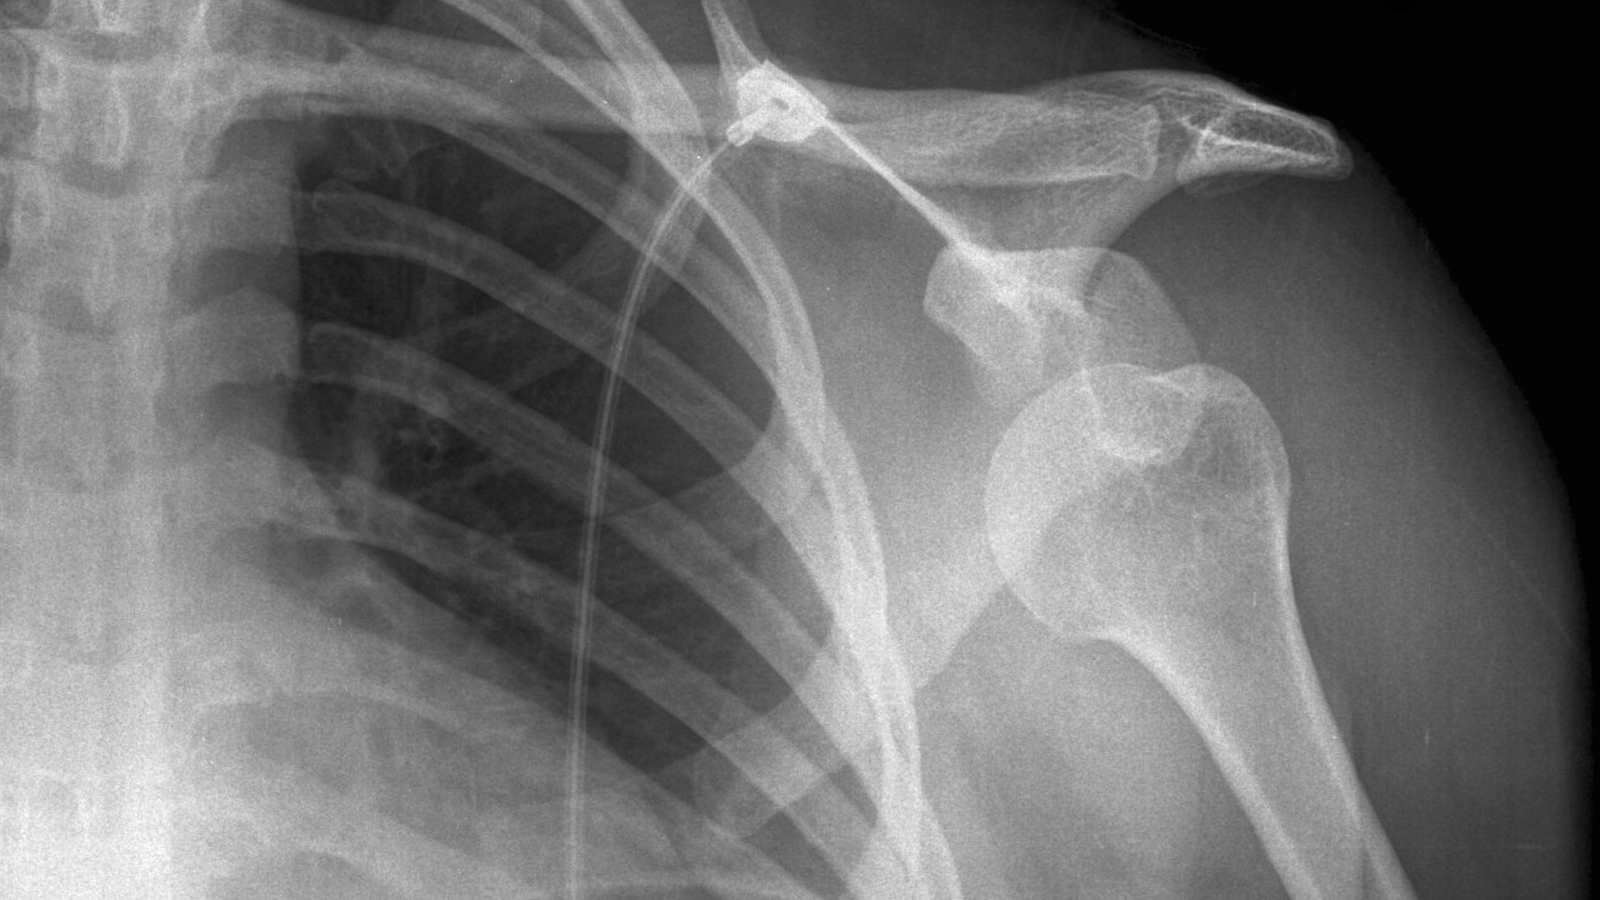

From veencanada.com

Radiography for Veterinary Technicians VEEN Canada Veterinary Radiography Ug Formula Say you have a sch 40 6.00 pipe weld to examine. An indistinct ‘penumbra’ area around the. Geometric unsharpness (ug) is determined as follows: Given these parameters, give your answers in inches. Geometric unsharpness is a numerical value related to the ‘fuzziness’ of a radiographic image, i.e. Broadly, if one value of unsharpness (u g or u f ) is. Radiography Ug Formula.